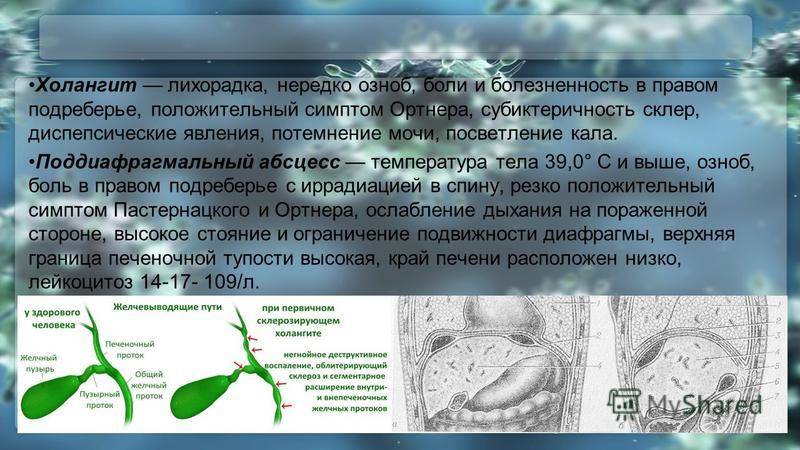

Фотографии и изображения, связанные с симптомами первичного склерозирующего холангита

Раздел: Кладезь мудрости